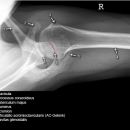

Schulter nach Morrison oder Outlet View

Indikation

v.a. Impingementsyndrom: Beurteilung des Akromions, des AC-Gelenks, evtl. hilfreich zur Diagnostik von Luxationen

Beurteilungskriterien

- Impingementsyndrom (2): Neigungswinkel des Akromions -> Je gebogener bzw. hakenförmiger desto höher ist die Wahrscheinlichkeit. Radiologische Befunde: Zystenbildung im Bereich des Tuberculum majus? Subchondrale Sklerosierung am Tuberculum majus oder subacromiale Osteophytenbildung? Verkalkungen im Verlauf der Supraspinatussehne?

- subacrominalen Raumes: normalerweise 1 - 1,5 cm, < 10 mm -> wahrscheinlich, < 6 mm -> sicher pathologisch